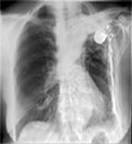

Sala de radiografie de inalta performanta

O multime de pacienti si o mare varietate de aplicatii si proiectii sunt caracteristicile unei Sali de radiografie de inalta performanta. In aceasta sala este esentiala influenta reciproca a aparatelor.Fiecare component trebuie sa se combine cu incredere, fara intarziere si sa ofere imagini de o calitate remarcabila inca de la prima captare a imaginilor.